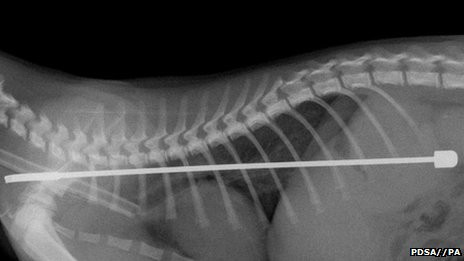

![]() Ảnh chụp X-quang |

Vị bác sỹ này tiên đoán rằng có vẻ như con mèo đang đùa nghịch với chiếc ăng ten thì vô tình bị tai nạn và nuốt chiếc ăng ten vào bụng. Thật may mắn là Alphie đã nuốt phần đầu ăng ten vào trước. Nếu đầu bị gãy bị nuốt vào trong, nó có thể làm xây xát dạ dày của chú và gây tổn thương ruột do đó dẫn tới tử vong.